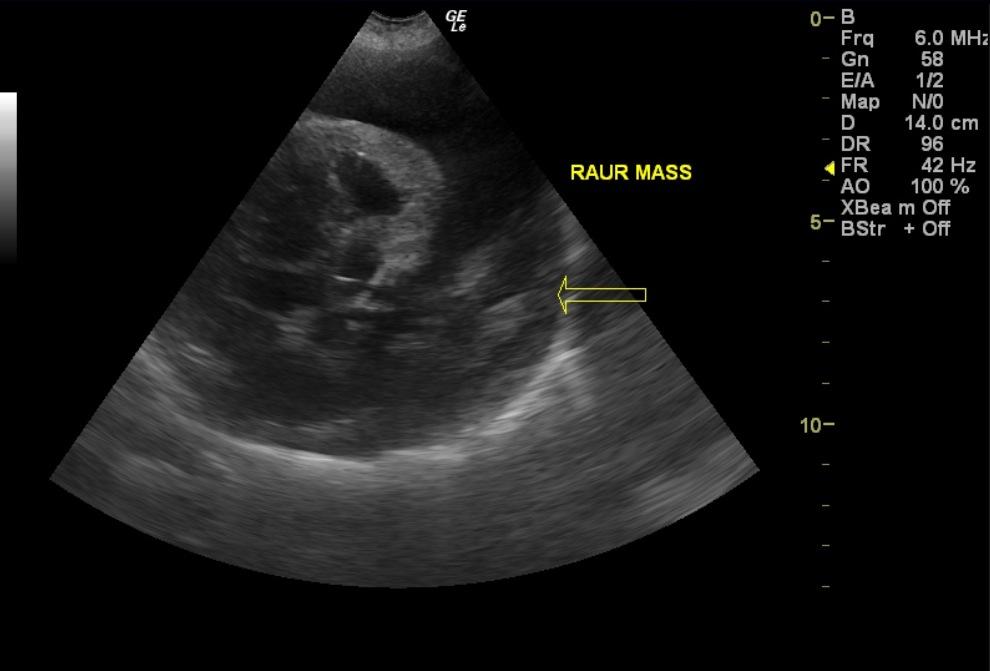

A 10-year-old SF Rottweiler cross was presented with a history of lethargy and not doing right. On physical examination depression and polypnea was evident. Abnormalities on serum biochemistry were elevated liver enzyme activity. Cardiomegaly was present on survey radiographs. Blood pressure was normal (140).